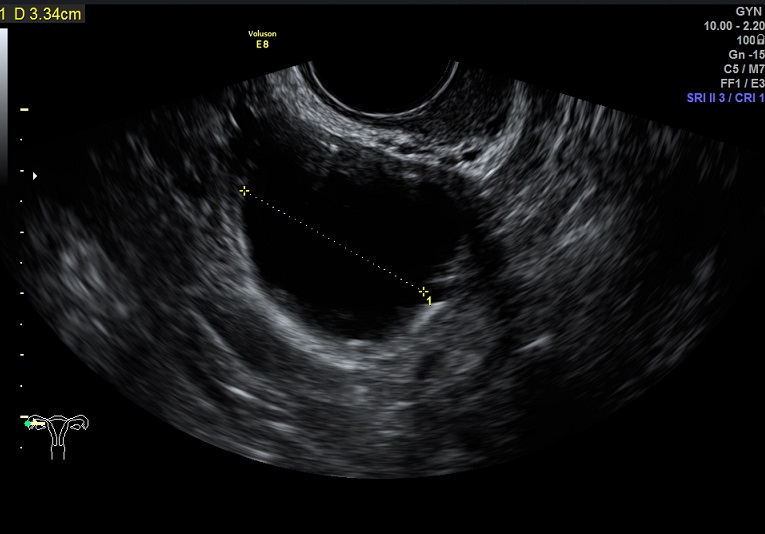

女性,24岁,原发性不孕1年余。

2015-3-10 月经第19天检查

左卵巢黄体 右卵巢囊性结构